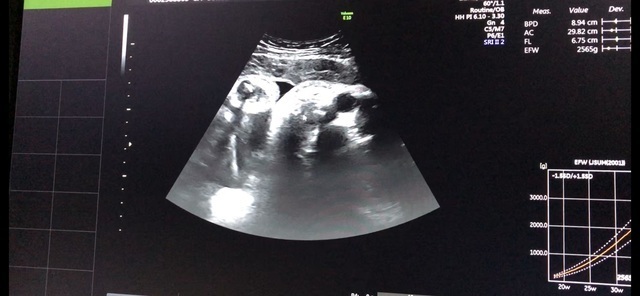

38週0日(38w0d・男の子)|ゆうこ_o さん(28歳)

エコー写真撮影時のエピソード:

臨月に入り、いつ産まれるかそわそわしていた。エコー写真を見て、ほっぺたがふっくらしたり、体重が2500グラムを超えていて、いよいよだなと楽しみになった。でも早くからそわそわした割に、予定日9日超過し、予定日超過してからは、ストレスも感じた。